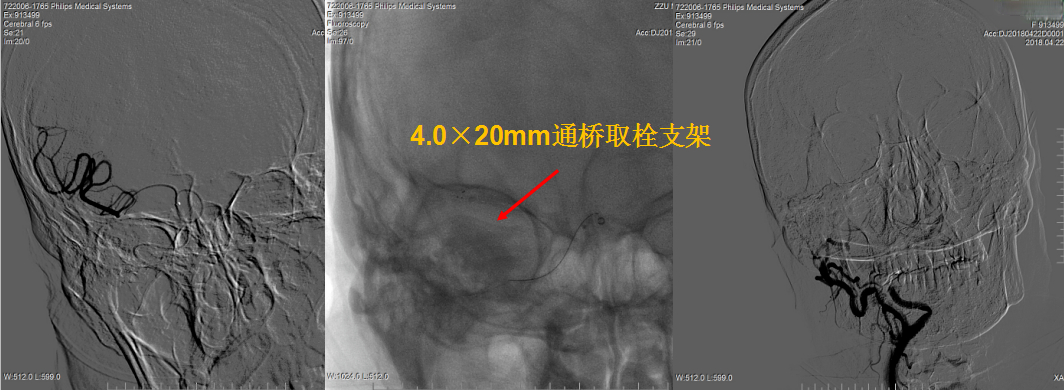

右侧颈内动脉造影显示右侧颈内动脉闭塞。

侧枝代偿差。

选择4.0×20mm支架,采用swim技术取栓2次,取出少量暗红色血栓,颈动脉造影未见血流恢复,单支架取栓无效。

考虑血栓负荷量大,遂采用双支架取栓技术。